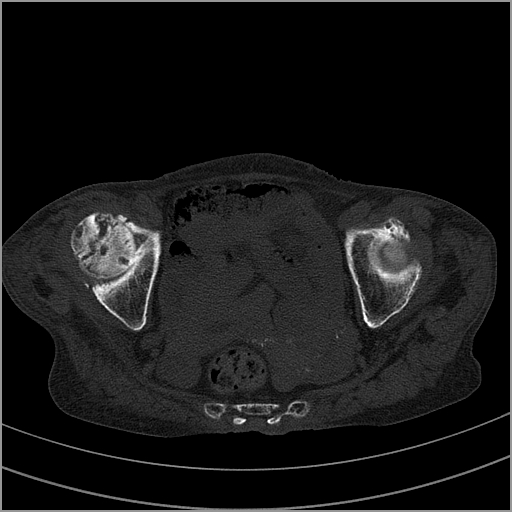

以下是引用老爱克斯新网客在2009-2-3 19:42:00的发言:[br]右侧髋臼及右侧股骨头可见明显骨质破坏,以溶骨性破坏为主,无明显硬化,髋关节间隙变窄,周围软组织明显肿胀,密度不均,脂肪间隙消失。[br] 诊断:右侧髋关节感染性病变,右侧髋关节结核的可能大。[br] 鉴别诊断:1.股骨头缺血坏死,单纯股骨头缺血坏死病例不会累积髋臼骨破坏。2。退行性关节炎,以骨质增生为主,伴有关节面硬化,骨质破坏呈多发小囊状破坏为主,其周围可见硬化环。3.股骨头缺血坏死晚期(第四期)骨质破坏可伴髋关节退行性变,可有骨质增生,但此时骨破坏以股骨头破坏为主,不应该伴有髋臼骨质破坏,因为股骨头的骨破坏是因血运中断,而没有髋臼的血运中断,又没有细菌的感染,怎么能造成髋臼的骨破坏呢。